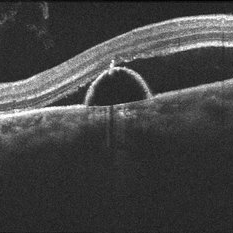

Macular Hole POD 1 OCT

Jun 21 2016 by John S. King, MD

POD 1 - hole closed as seen on OCT

Condition/keywords: full thickness macular hole, optical coherence tomography (OCT)